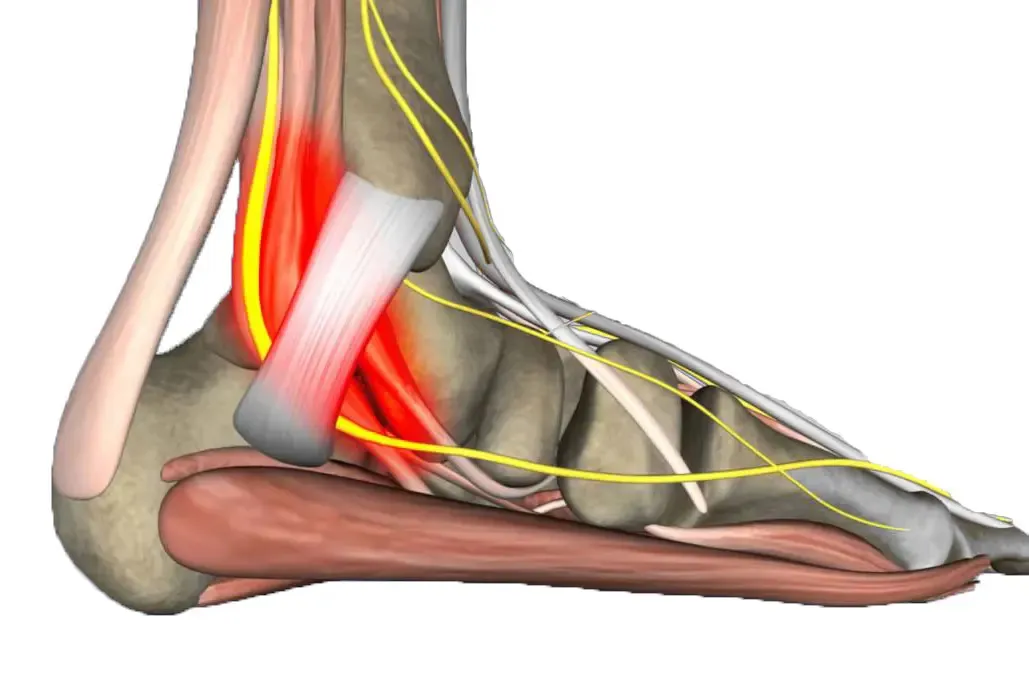

Pero no nos quedamos solo en la exploración visual. Utilizamos ecografía diagnóstica para valorar la localización exacta de las lesiones, su profundidad, características tisulares y vascularización. Estos datos son esenciales para el diagnóstico diferencial y para planificar el tratamiento más adecuado.

Figura 6: El estudio ecográfico nos permite ver estructuras que no son visibles a simple vista y planificar el tratamiento con precisión.

- Estudio ecográfico: Valoración de profundidad y características tisulares